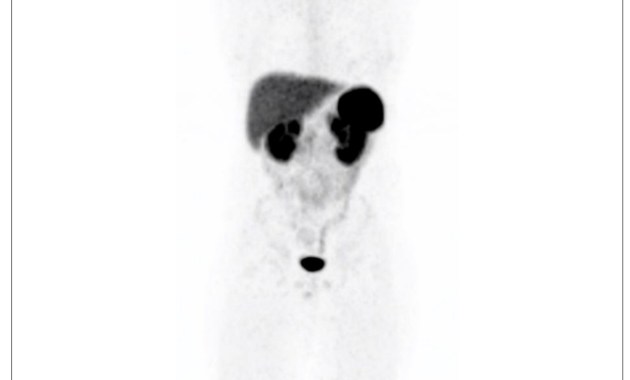

Özet Bu makale, nöroendokrin tümörlerin (NET) görüntülemesinde kullanılan Ga-68 DOTATATE PET/CT’nin normal varyantlarını, tuzaklarını ve artefaktlarını incelemektedir. Ga-68 DOTATATE, hücre yüzeylerindeki somatostatin reseptörlerini (özellikle SSTR2) hedefleyen bir somatostatin analoğudur ve […]